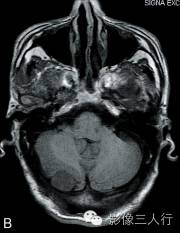

A.T2WI横断面;B.T1WI横断面;C、D、E.增强横断面、矢状面、冠状面;F.HE×100

图A、B:平扫MRI显示右侧小脑后缘类圆形结节状病灶,大小约1.4cm×2.0cm×1.8cm,在T2WI呈稍高信号,T1WI为稍低信号,边界清楚,信号均匀,局部脑组织受压内移。图C~E:Gd-DTPA增强扫描显示结节呈较均匀明显强化,病灶边缘清楚,其中在横轴位图像显示肿瘤中央部分强化较周围明显,且类似日光放射状。矢状位、冠状位图像见肿块强化变均匀一致,紧贴小脑后方硬脑膜或颅骨,但未见明显硬脑膜尾征。